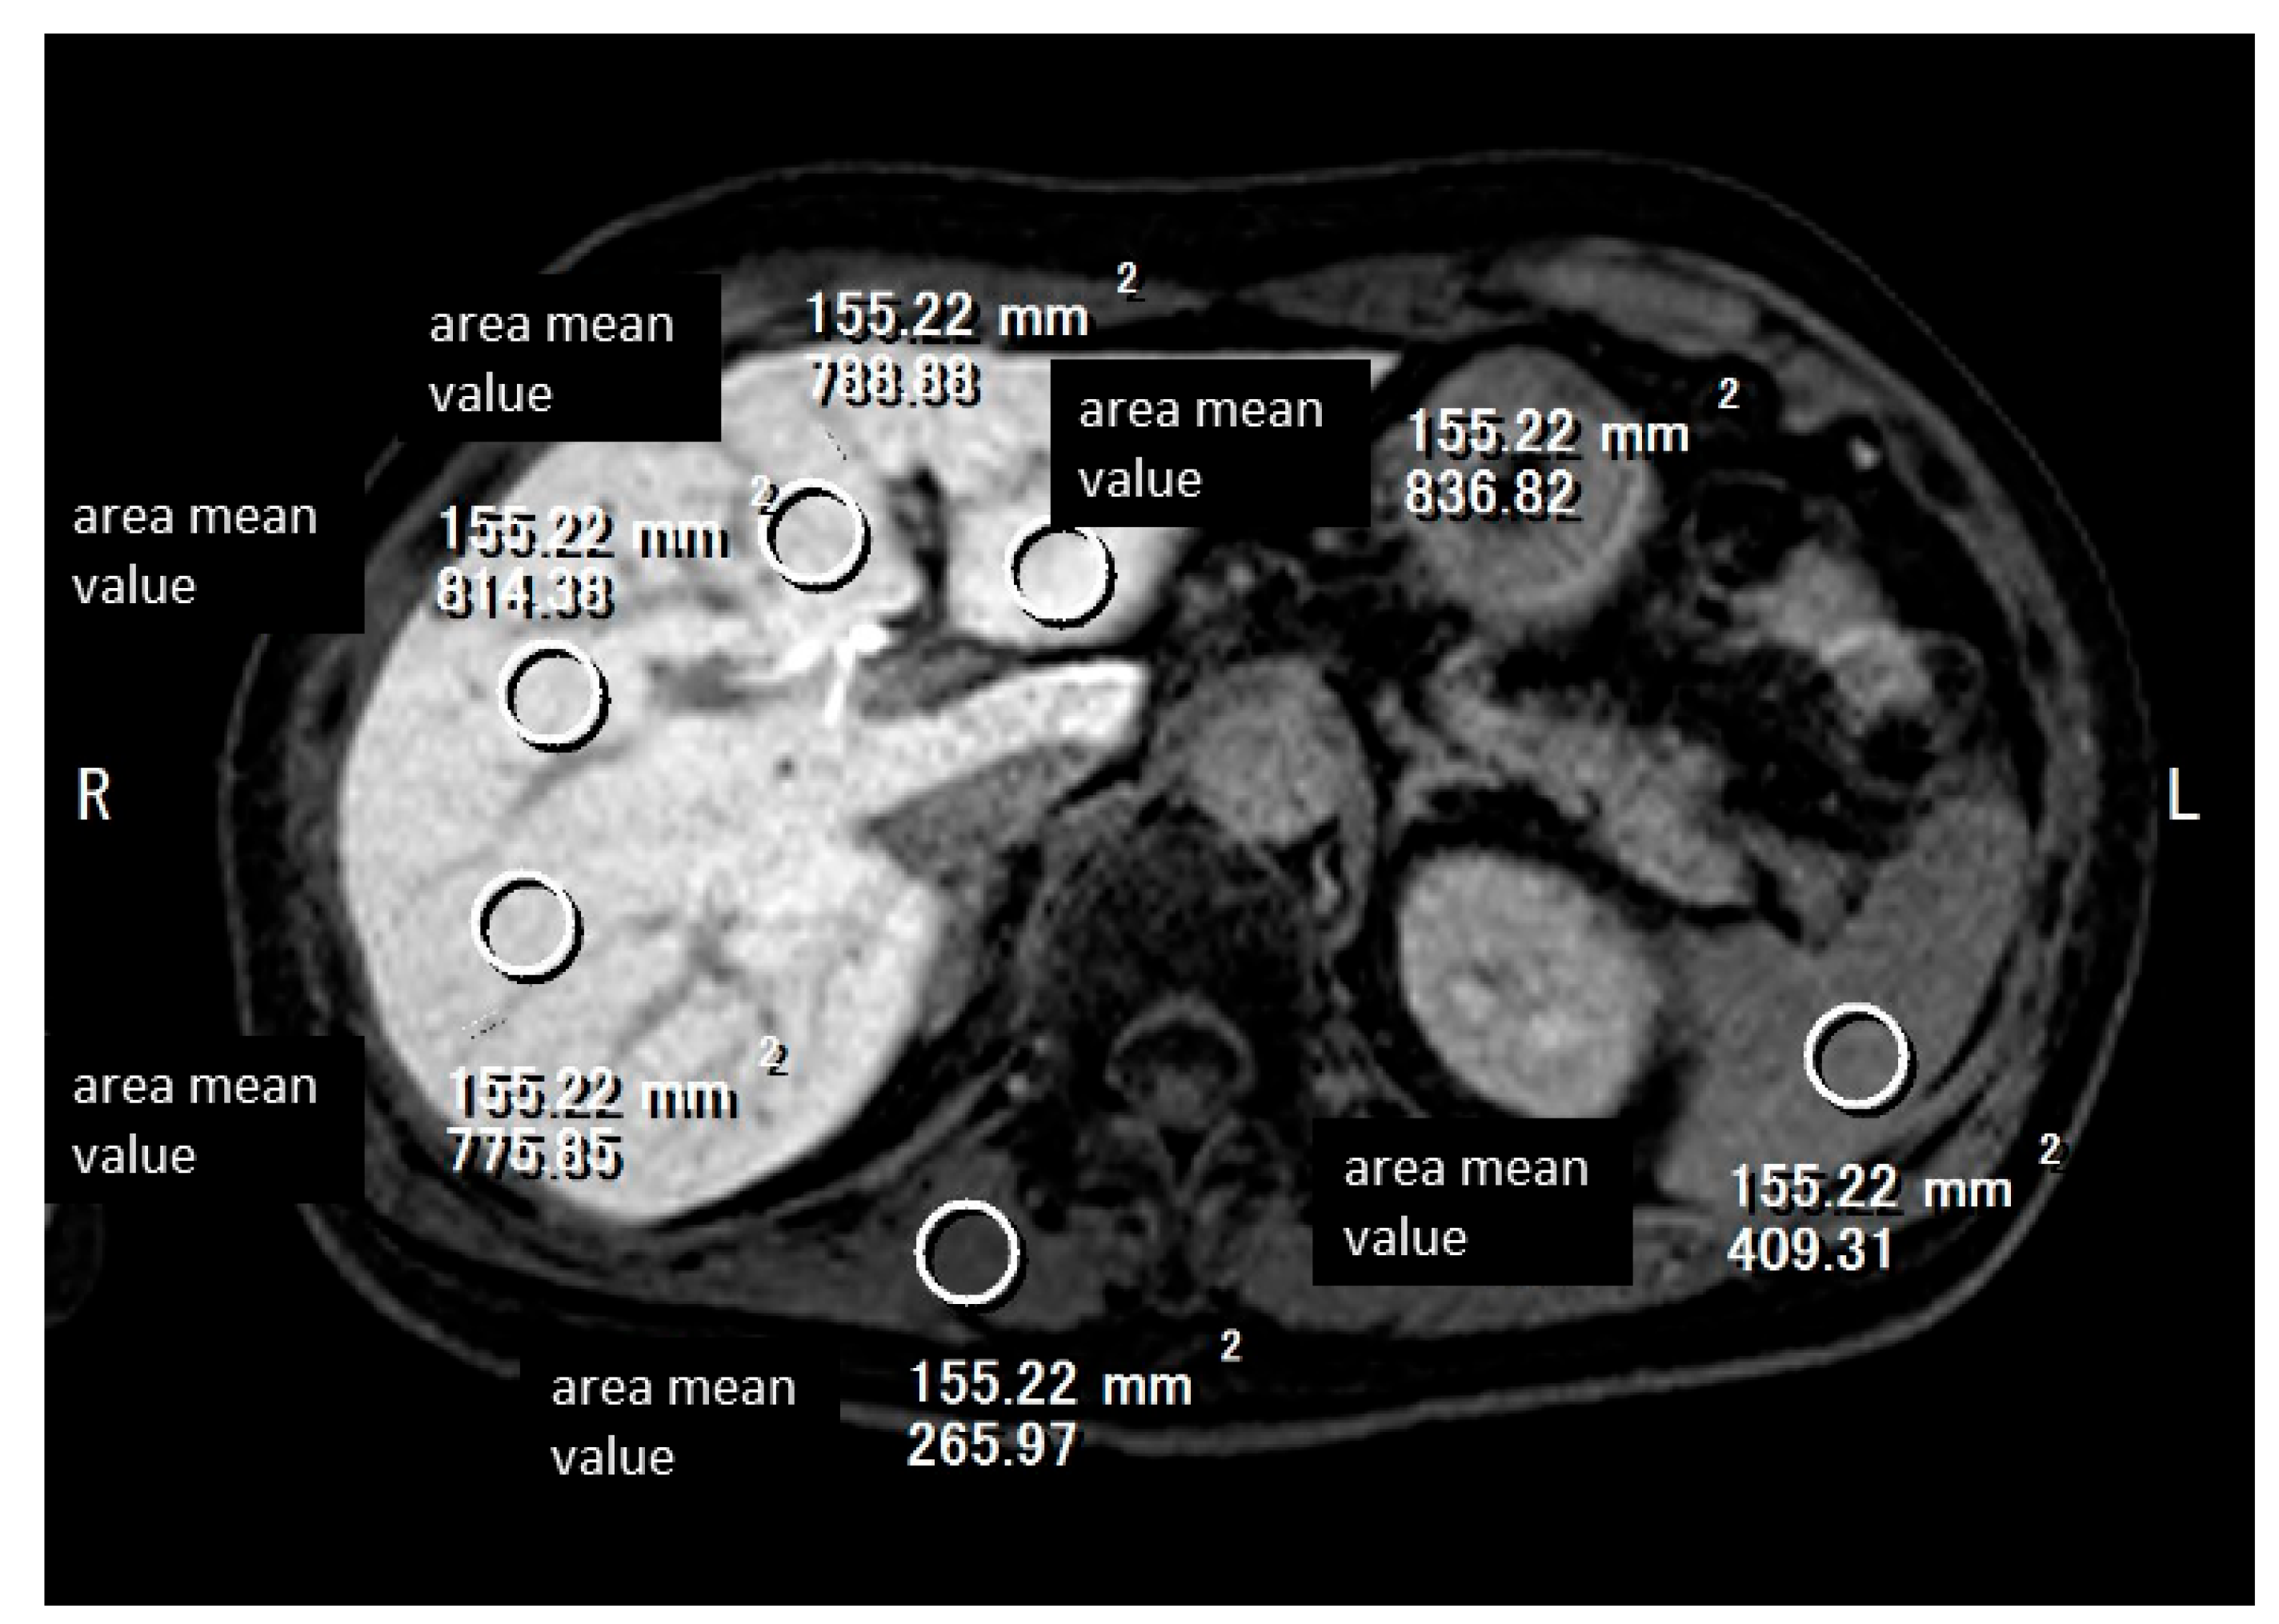

- Tago, K.; Tsukada, J.; Sudo, N.; Shibutani, K.; Okada, M.; Abe, H.; Ibukuro, K.; Higaki, T.; Takayama, T. Comparison between CT volumetry and extracellular volume fraction using liver dynamic CT for the predictive ability of liver fibrosis in patients with hepatocellular carcinoma. Eur. Radiol. 2022, 32, 7555–7565. [Google Scholar] [CrossRef] [PubMed]

- Shinagawa, Y.; Sakamoto, K.; Sato, K.; Ito, E.; Urakawa, H.; Yoshimitsu, K. Usefulness of new subtraction algorithm in estimating degree of liver fibrosis by calculating extracellular volume fraction obtained from routine liver CT protocol equilibrium phase data: Preliminary experience. Eur. J. Radiol. 2018, 103, 99–104. [Google Scholar] [CrossRef] [PubMed]

- Mizuno, M.; Tago, K.; Okada, M.; Nakazawa, Y.; Arakane, T.; Yoshikawa, H.; Abe, H.; Matsumoto, N.; Higaki, T.; Okamura, Y.; et al. Extracellular volume by dual energy CT, hepatic reserve capacity scoring, CT. volumetry and Transient-elastographyfor estimating liver fibrosis. Sci. Rep. 2023, 13, 22038. [Google Scholar] [CrossRef]